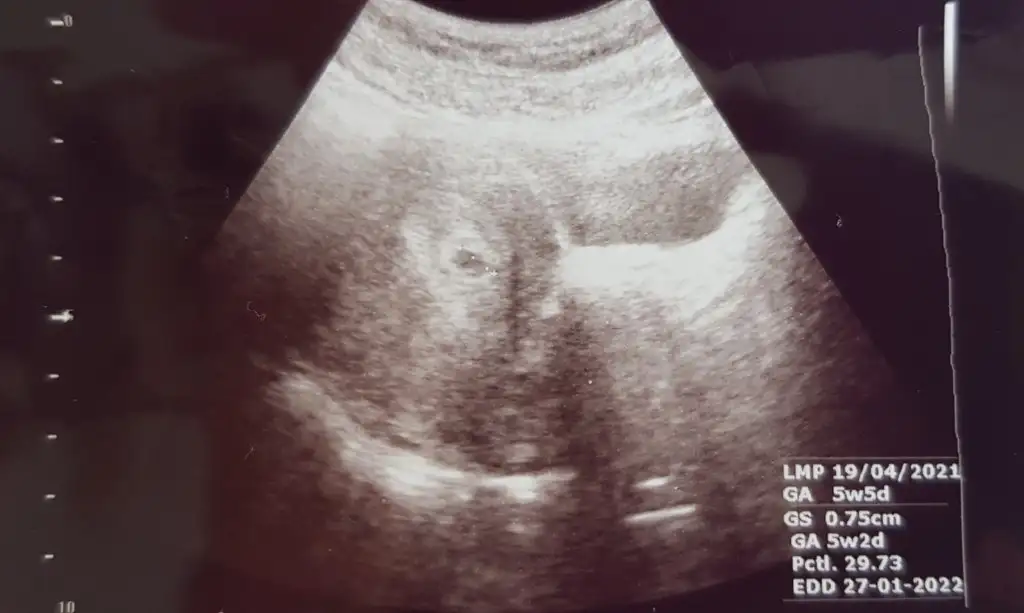

Çok sağol canım♡ Aynen fotoğrafı verdiler, ben de şimdi yükliyim gösteriyim. Ama buğulu sanki benimki seninkine göre😄 Arkalarda mi saklanıyor napiyor 🤔

Asistanı regl tarihimi sorup 5+5dedi ama doktorum bişey demedi o konuda. Haftaya tekrar geleceksin dedi. Ondan sonra da 4haftada 1 görüşücez dedi. Bu hafta bile gözükmezken 1 haftada nasıl kalbi atıcak minnoşun merak ediyorum 😅